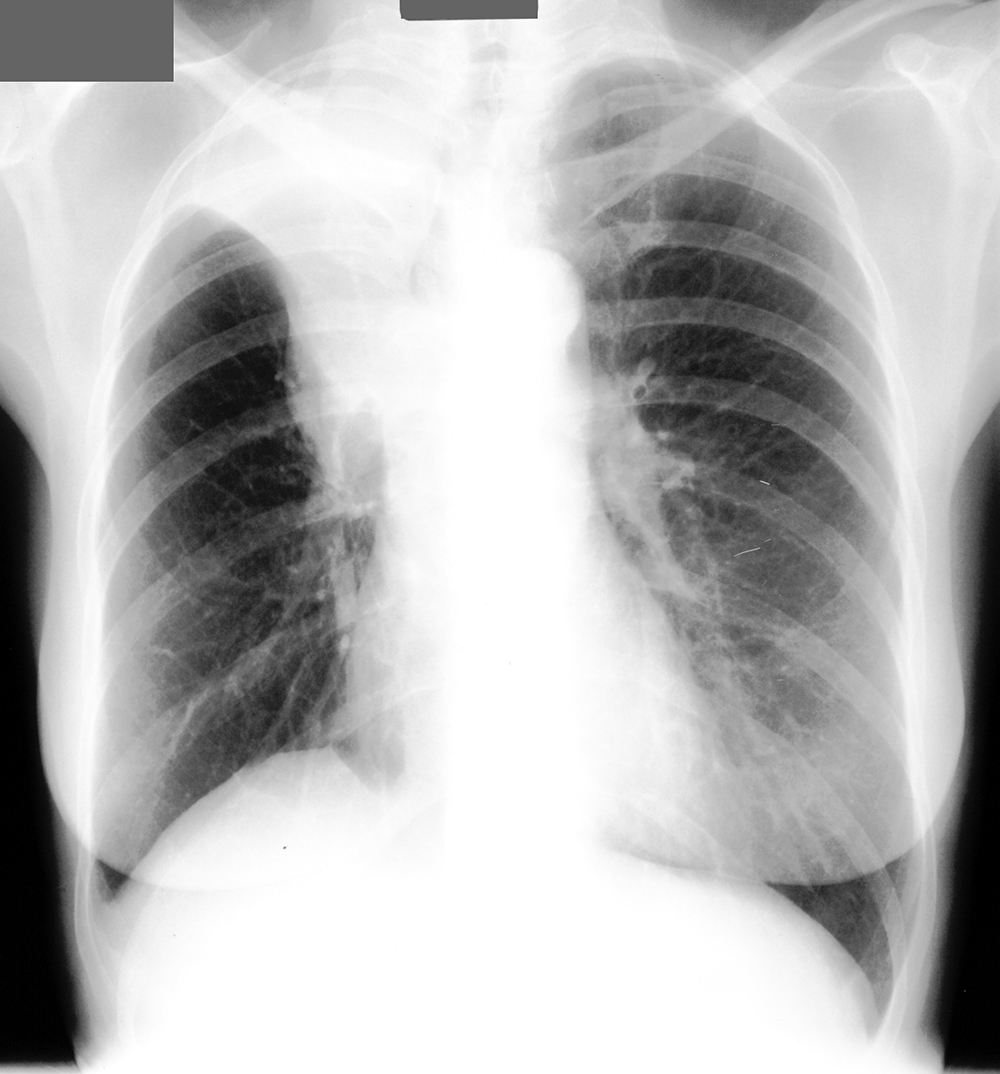

Topic 1

advanced case PNA

Further Explanation: